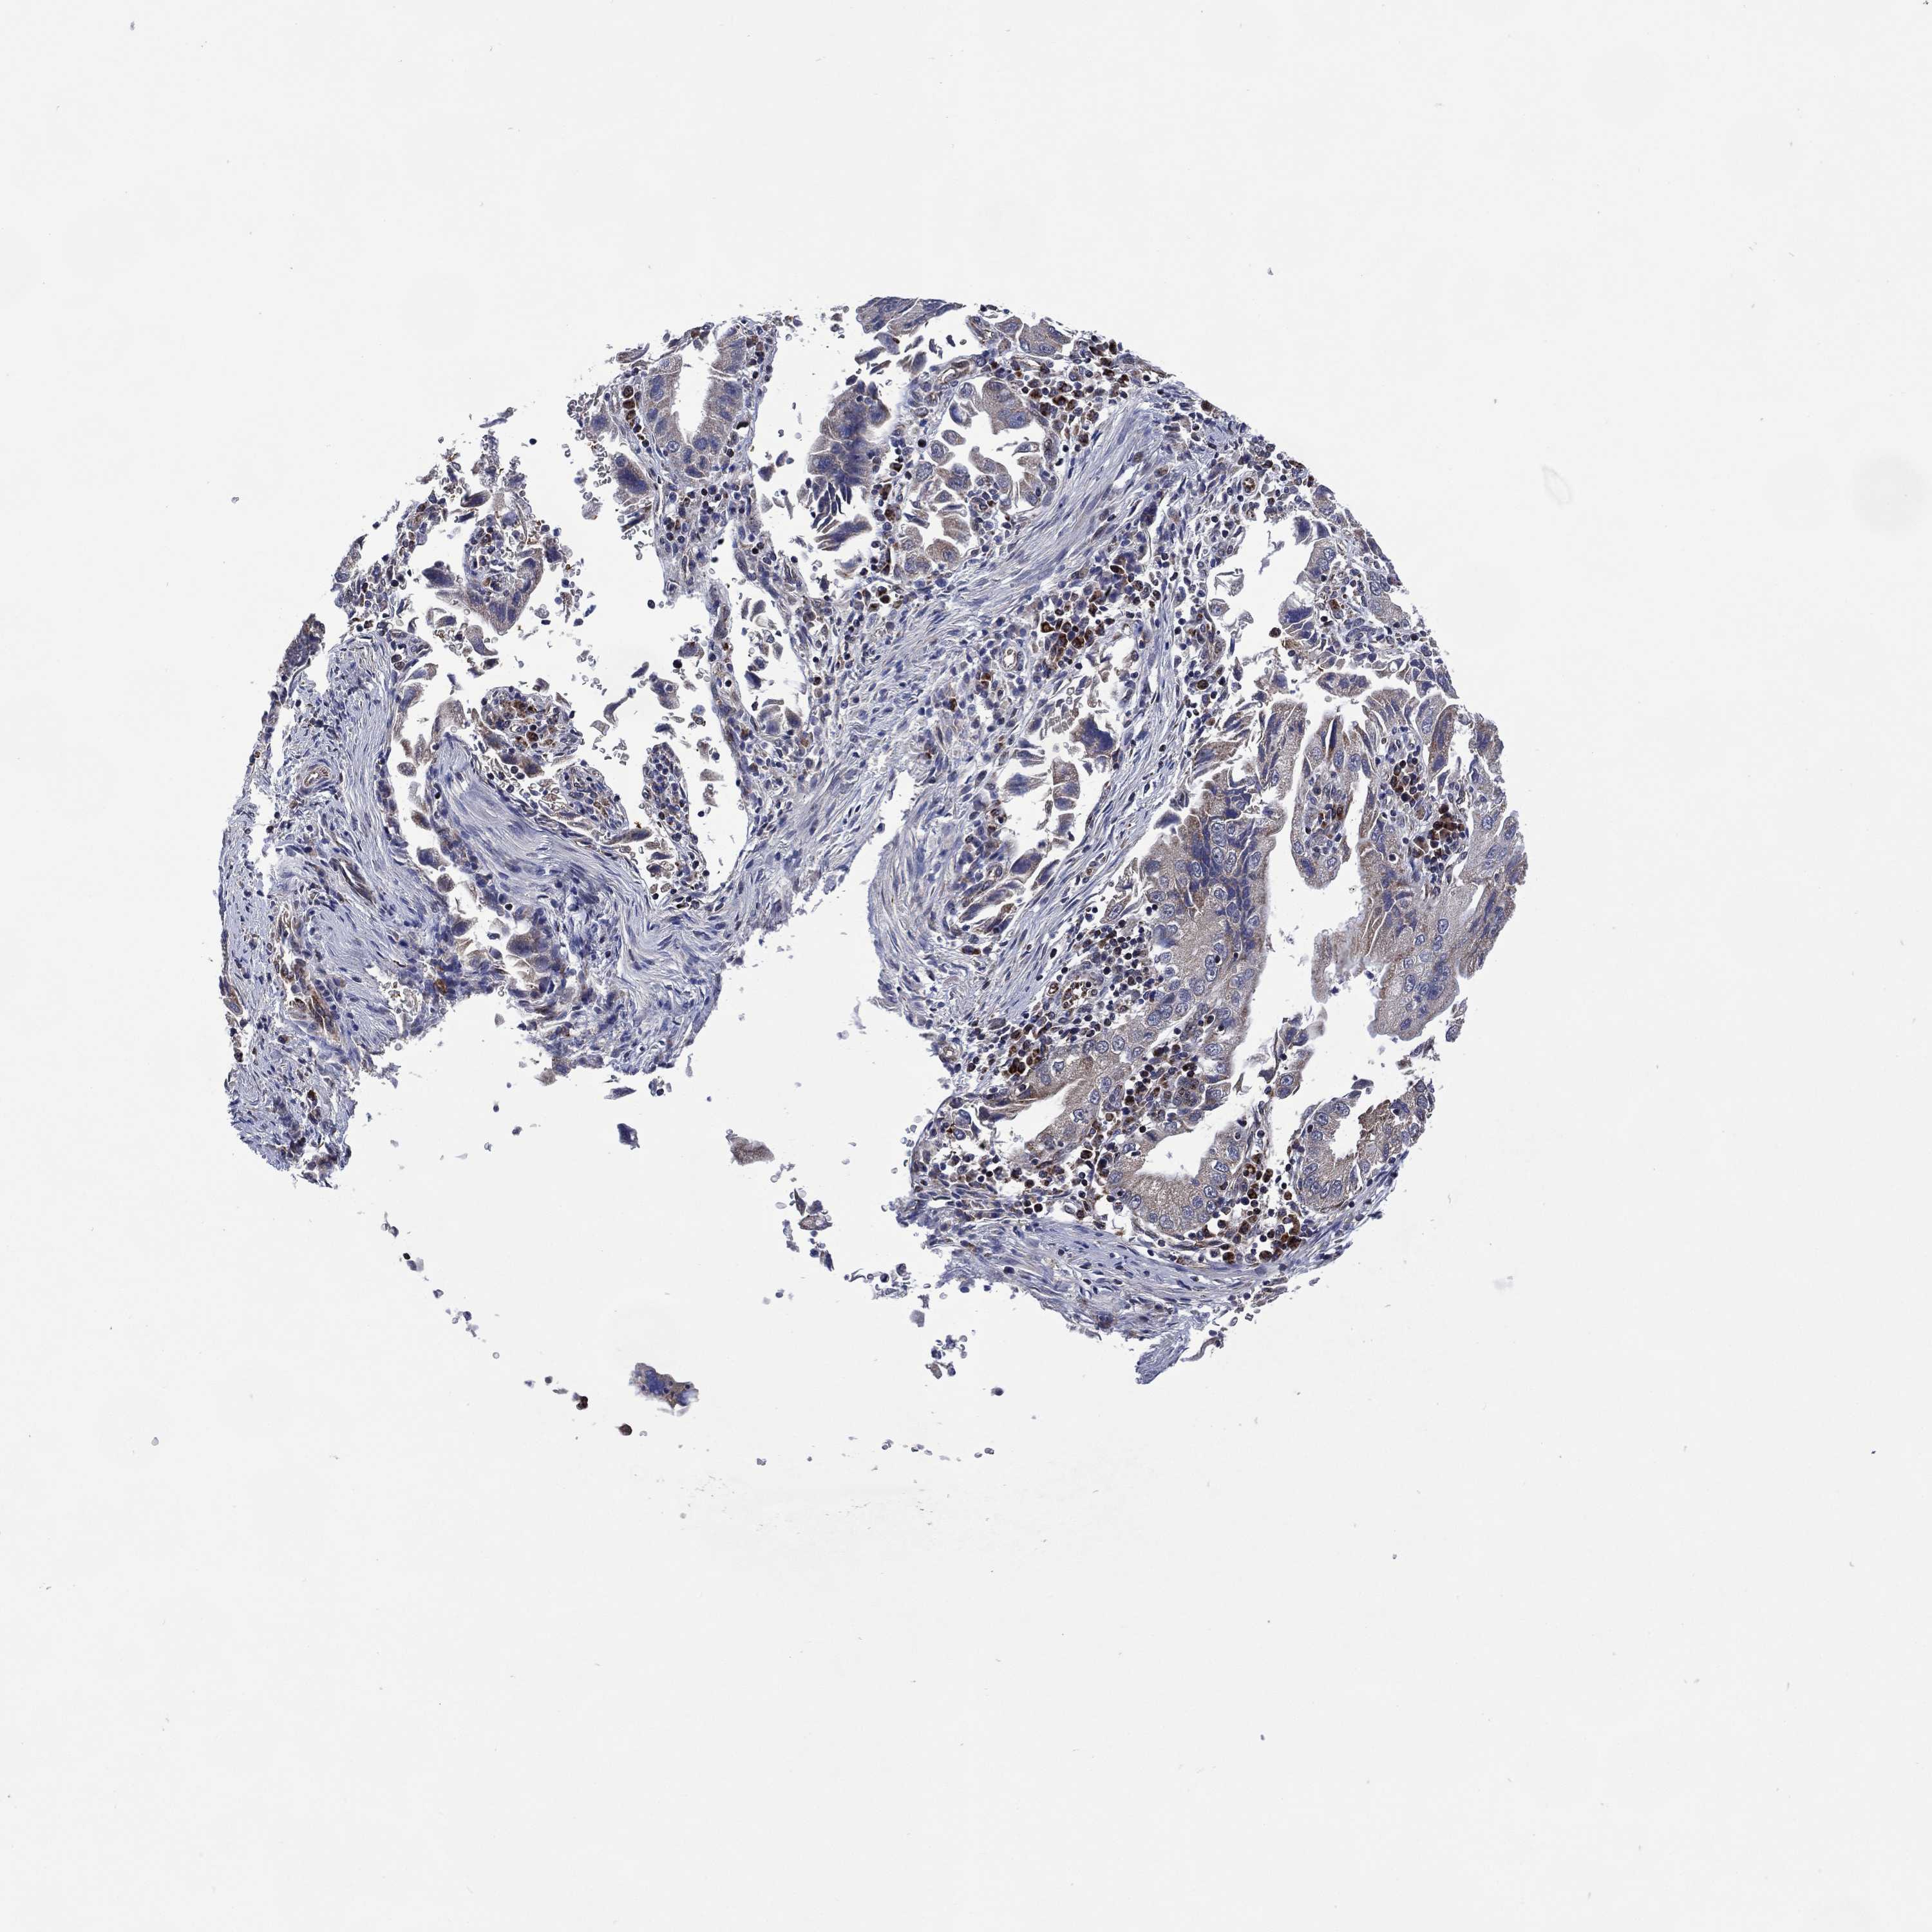

STOMACH CANCER - Protein expressioni

A mouse-over function shows sample information and annotation data. Click on an image to view it in a full screen mode. Samples can be filtered based on level of antibody staining by selecting one or several of the following categories: high, medium, low and not detected. The assay and annotation is described here.

Note that samples used for immunohistochemistry by the Human Protein Atlas do not correspond to samples in the TCGA dataset.

Antibody stainingi

Antibody staining in the annotated cell types in the current human tissue is reported as not detected, low, medium, or high, based on conventional immunohistochemistry profiling in selected tissues. This score is based on the combination of the staining intensity and fraction of stained cells.

Each image is clickable and will lead to virtual microscopy that enables deeper exploration of all samples and also displays staining intensity scores, fraction scores and subcellular localization as well as patient and tissue information for each sample.

Antibody HPA077228

Staining

High

Medium

Low

Not detected

Intensity

Strong

Moderate

Weak

Negative

Quantity

>75%

75%-25%

<25%

None

Location

Nuclear

Cytoplasmic/membranous

Cytoplasmic/membranous,nuclear

Adenocarcinoma, NOS

Adenocarcinoma, High grade